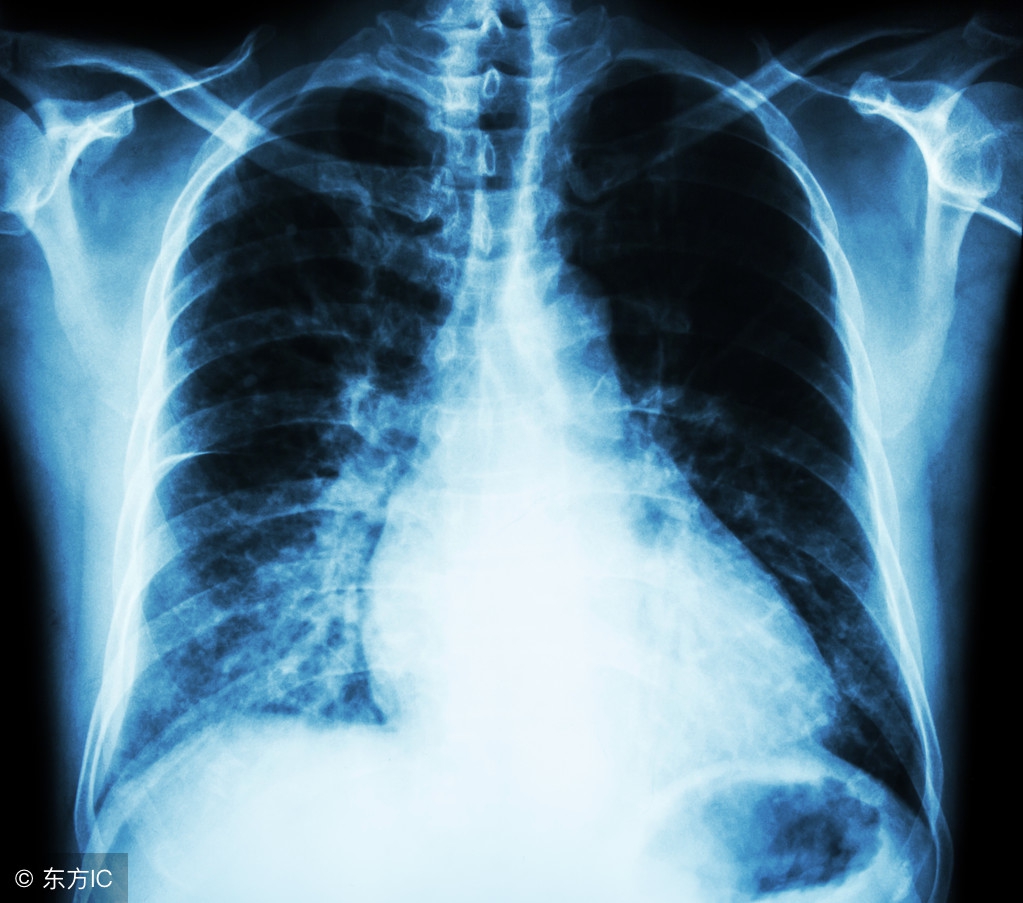

肺部检查发现结节影 (体检发现肺条索结节状高密度影)

有患者问:左肺结节17*14mm,周围见少许条索状及斑点状影,纵隔无移位,气管,主支气管,双侧主支气管及其分支通畅。右上肺少许纤维增值灶是什么情况?

其实对于大于一公分的肺部结节一定要引起重视,因为大量的研究证实,结节大于一公分以后它的恶性程度可能性就会增加,而且随着结节逐渐增大,恶性程度的可能性也会越来越高。另外,需要注意的是,肺部结节的性质也是多种多样的。

具体来说,肺小结节其实是一个影像学的概念,一般是指在肺实质中的病灶,小于三公分的实性病灶就叫肺结节,大于三公分的叫做肿块。其中对小于一公分的就叫做肺小结节,小于五毫米的就叫微小结节。

但是根据描述,结节周围有一些炎性病灶和条索影,在结节两个新的判断中有很重要的一条就是卫星病灶,意思就是在结节的周围有一些小的斑斑点点的病灶。一般这是结核等感染性疾病的典型影像学表现。